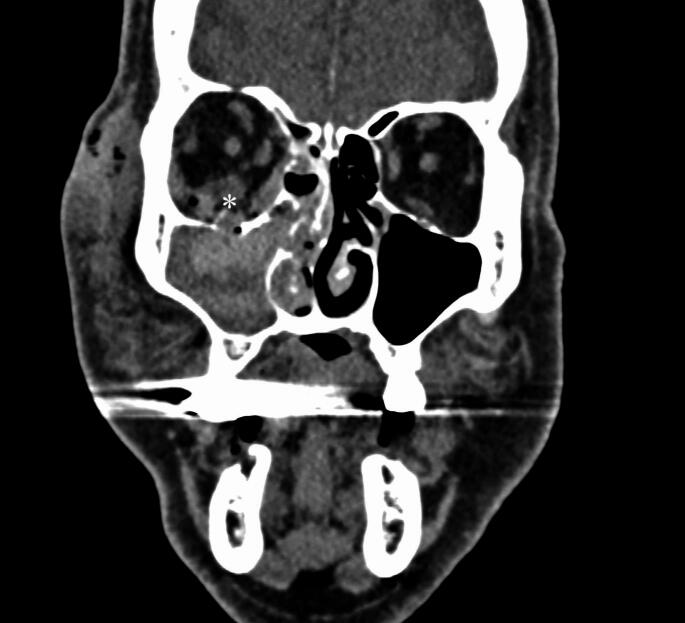

Results: Of the 2149 patients with orbital fractures, 28 (1.3%) presented with acute RBH, including two bilateral haematomas, bringing the total number of RBHs to 30. Specific injury mechanisms were statistically associated with RBH (p = 0.005), with high-energy injuries being the most frequent cause. The prevalence of RBH was higher in bilateral than unilateral fractures (3.1% vs. 1.1%) (p = 0.023). Among unilateral fractures, RBH was most strongly linked to orbital roof and rim fractures. Tenting or tuliped-like appearance on computed tomography and absence of pupillary light reflex were more common in patients with permanent vision loss. Type of surgical approach did not affect visual outcome.

Conclusion: Acute RBH appears to occur more frequently in patients with orbital fractures than previously reported. Clinicians managing facial fractures need to be trained to diagnose RBH promptly and identify indicators of potential vision loss, particularly tenting on radiological images and changes in pupillary reflex.